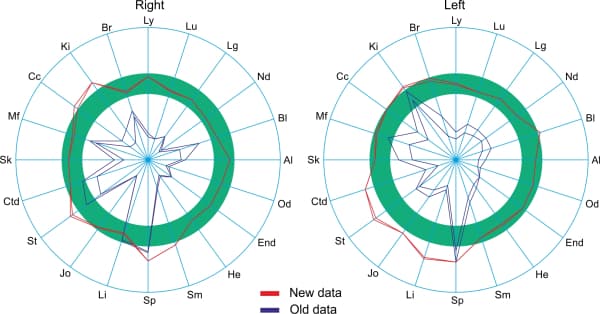

Test subject’s circular charts before the Aires Defender (Fig. 3) and after the Aires Defender (Fig. 4):

The blue line is the left side. The green line is the right side. The red dashed line is the generalized measurement.

Before using the Aires Defender, a pronounced asymmetry of the circular charts was observed due to the depression of some meridians and the activation of others.

After the effect, the chart’s asymmetry was substantially reduced and the majority of the measures were in the normal range (green band).

The test subject’s circular charts at the beginning of the workday (before application of the Aires Defender) (Fig. 3) and after working for 6 hours with the Aires Defender (Fig. 4).

Before applying the Aires Defender, a moderate asymmetry of the charts was observed due to the depression of some meridians and the activation of other meridians.

After 6 hours of working under the protection of the Aires Defender, the circular chart became more symmetric and measurements for the majority of the meridians were in the normal range of values (green band).